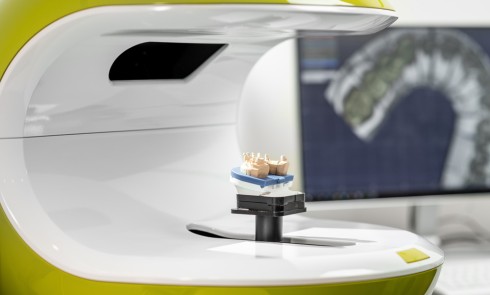

Le modèle de travail est fabriqué au laboratoire, des piliers CFAO Atlantis™ sont réalisés en fonction du bridge antagoniste transitoire.

Le modèle de travail est fabriqué au laboratoire, des piliers CFAO Atlantis™ sont réalisés en fonction du bridge antagoniste transitoire.